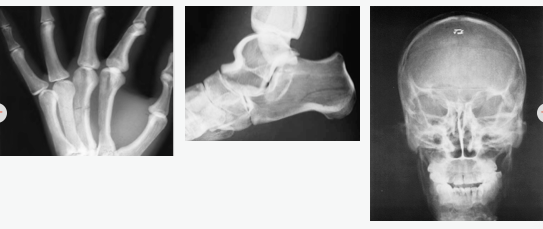

病理和创伤

头部 下颌髁突骨折的头部移位

左侧颧额骨分离性骨折

左眶下缘台阶畸形

下颌骨骨折伴骨缺失

鼻骨骨折

胳膊 左臂桡骨、尺骨移位性骨折

左手第三和第四掌骨骨折

脚部 足跟骨右移位角骨折